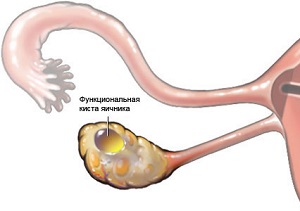

Кісти яєчників і вагітність